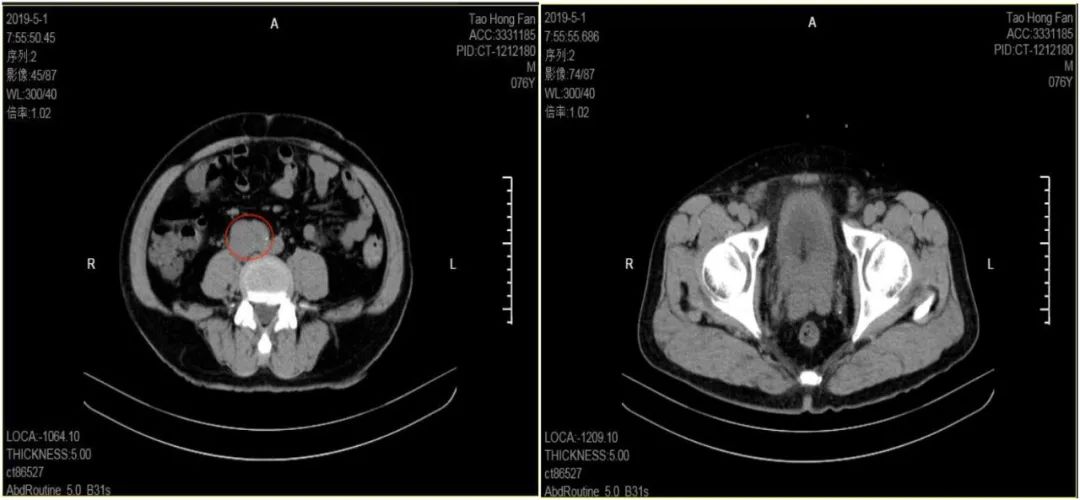

▍ 检查结果 实验室检查:总前列腺特异抗原(tPSA)59.586ng/ml,碱性磷酸酶363IU/L。CTU:盆腔内及腹膜后多发淋巴结肿大(图1)。

图1 CTU结果